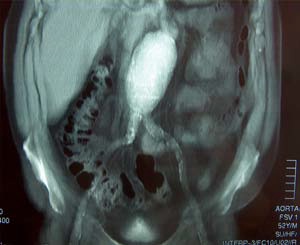

Λεπτομέρειες για την ανατομική δομή του ανευρύσματος που είναι χρήσιμες για τον σχεδιασμό της επεμβατικής αντιμετώπισης παρέχονται από την αξονική τομογραφία άνω και κάτω κοιλίας καθώς επίσης και από τη νεότερη μέθοδο ψηφιακής απεικόνισης, spiral CT